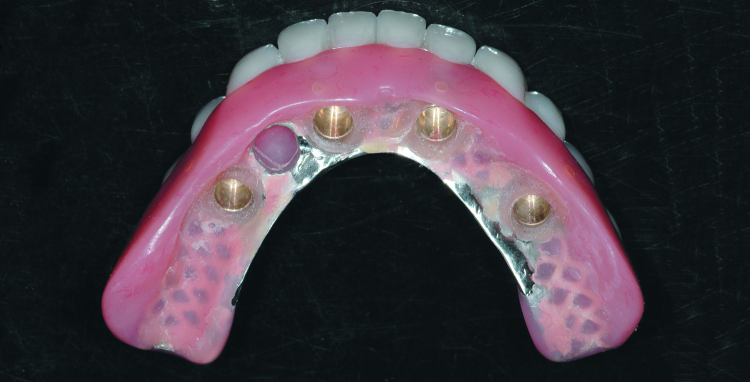

Fig. 11: Completed laboratory restoration showing the metal frame and recessed area to receive the SynCone caps.

When received, the Atlantis Conus Abutments were secured to the working cast with abutment screws, along with four prefabricated SynCone caps (Figs. 8 & 9). The caps were seated onto the abutments and sent to the dental laboratory to be impressed. The impression was poured twice, one in improved dental stone and one in refractory material for fabrication of a cast metal frame. While waiting for the frame to be completed, final try-in appointments for the denture set-up were completed, and the patient approved fabrication of the dentures.

The denture set-up with a final bite record were returned to the dental lab, the cast metal frame was seated on the improved dental stone cast and areas around the stone copy of the SynCone caps were blocked out prior to processing. The SynCone caps will be captured intraorally, rather than having them processed in the dental laboratory. All work was completed on the duplicate stone cast rather than the original working cast. The cast metal frame was opaqued to prevent grey show-through. The set-up was transferred to the cast with the metal frame and the dentures were processed (Figs. 10 & 11).